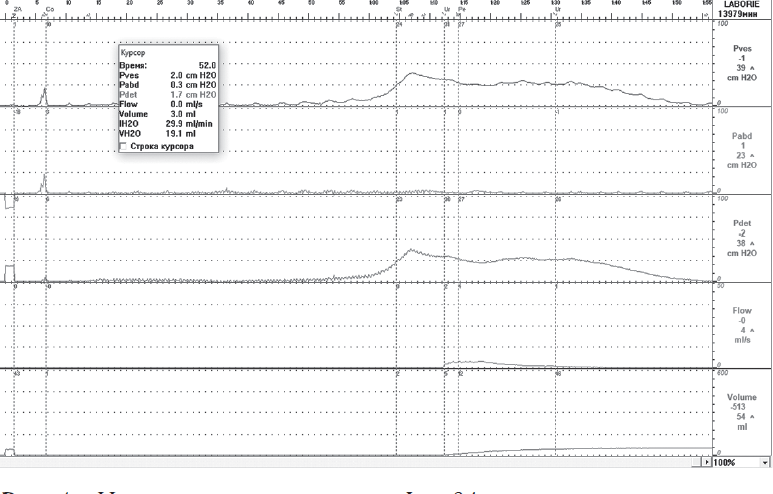

В ходе цистометрии наполнения при КУДИ у всех пациентов было подтверждено наличие гиперактивности детрузора. Максимальная цистометрическая емкость была снижена до 158,3 ± 72,2 мл. Спонтанное непроизвольное сокращение мочевого пузыря у некоторых пациентов начиналось уже при наполнении до 20 мл (рис. 1). Средний объем мочевого пузыря при возникновении первого эпизода гиперактивности составлял 155,0 ± 47,6 мл, максимальное давление детрузора в момент первого эпизода гиперактивности равнялось 17,57 ± 11,3 см H2O.

Рис. 1. Цистометрия пациентки Ф., 64 года, страдающей нейрогенной дисфункцией нижних мочевыводящих путей на фоне рассеянного склероза. Уродинамические признаки гиперактивности детрузора. Первое непроизвольное сокращение детрузора сопровождается ургентным недержанием мочи. V1IDC = 19,7 мл, PdetmaxIDC = 63,5 см Н2О

Fig. 1. Cystometry of patient F., 64 years old, suffering from multiple sclerosis with neurogenic detrusor overactivity. Urodynamic signs of detrusor hyperactivity. First involuntary detrusor contraction is accompanied by urge urinary incontinence. V1IDC = 19.7 ml, PdetmaxIDC = 63.5 cm H2O